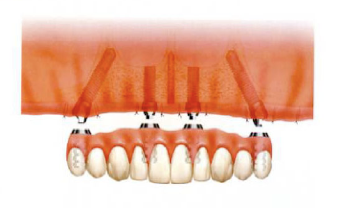

最低4本のインプラントを埋入し、それらを連結し、半日で固定式の仮歯まで入れて審美性、機能性を一日でとりもどせる革新的な治療。

1.従来インプラントは歯茎の中の骨に結合する3〜6ヶ月までは、歯をいれて噛ませることはできないと言われてきましたが、特殊な手術法によりインプラントを埋入し、4本〜6本を連結固定することにより、手術したその日からインプラントで食事を噛んでもらうことができるようになります。